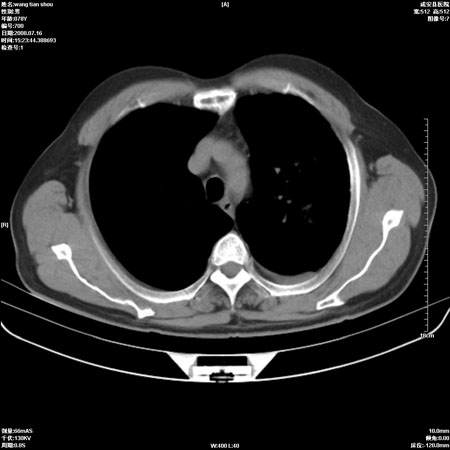

以下是引用qingjing在2008-7-16 19:55:00的发言:[br]1、左上肺不张并堵塞性炎症,建议支气管镜详查;[br]2、左侧胸腔少量积液。

以下是引用zsl6918在2008-7-17 8:09:00的发言:[br]肺炎胸膜炎可能性大,建议抗炎治疗后复查

以下是引用wzr在2008-7-16 20:26:00的发言:[br]左肺肺不张伴阻塞性肺炎!另:左侧胸腔少量积液。建议纤支镜检查!